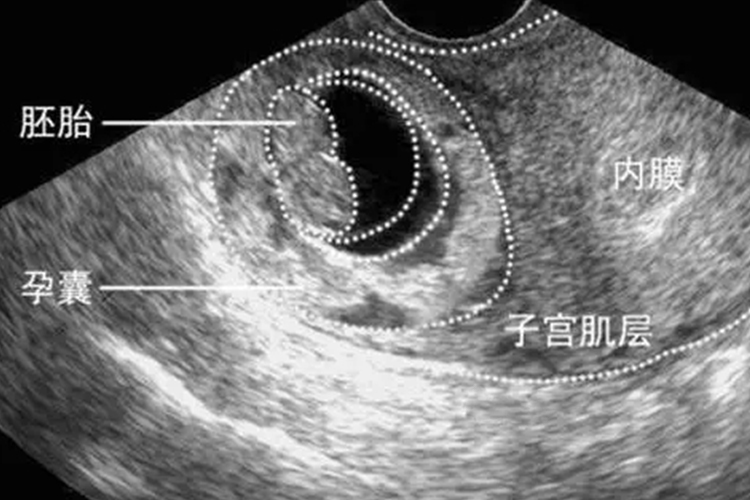

孕囊掉了即孕囊脱落,通常是自然流产或药物流产成功的标志,这一过程伴随着一系列身体反应,可能出现的症状包括阴道出血伴有血块、腹痛逐渐减轻等。